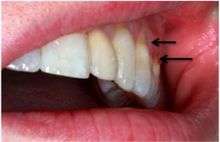

Abfraction lesions will generally occur in the region on the tooth where the greatest tensile stress is located. In statements such as these there is no comment on whether the lesions occur above or below the CEJ. One theory suggests that the abfraction lesions will only form above the CEJ.[5][6][7][8] However, it is assumed that the abfraction lesions will occur anywhere in the cervical areas of affected teeth. It is important to note that studies supporting this configuration of abfraction lesions also state that when there is more than one abnormally large tensile stress on a tooth two or more abfraction lesions can result on the one surface.[2]

When looking at abfraction lesions there are generally three shapes in which they appear, appearing as either wedge, saucer or mixed patterns.[5] Wedge and saucer shaped lesions are the most common, whereas mixed lesions are less frequently identified in the oral cavity.[5] In reference to figure 1, wedge shaped lesions have the sharpest internal line angles and saucer/mixed shaped lesions are either smooth internally, or a variety.